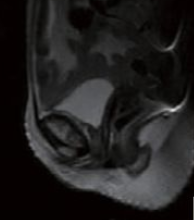

3.磁共振扫描(MRI)

影像学表现为:耻骨联合间隙可不同程度增宽,间隙内可见带状透亮间隙,单侧或双侧耻骨联合骨缘局限骨质硬化,少数囊变;耻骨联合骨缘锯齿状、鼠咬状、虫蚀状骨质破坏,边缘不光整,有时可见游离小骨块,早期骨质呈长T1长T2信号,晚期骨质均呈低信号。